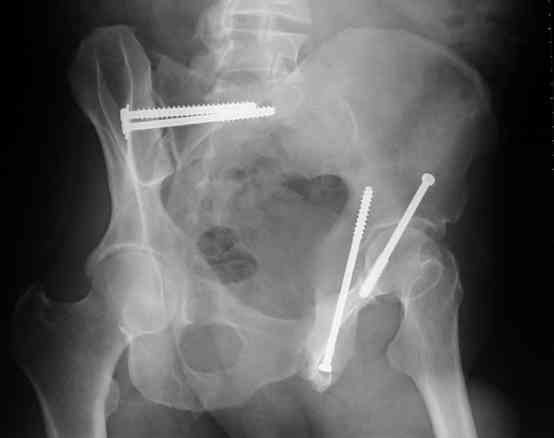

Screw Fixation

-AC Screw

-PC Screw

For Alex... here are some cannulated and 7mm screws for you... notice the fracture malreduction as indicated by the head subluxation on both views...this was a percutaneous technique without open reduction... I don¹t like it but there it is... the fixation technique is not at fault, because there was no open reduction of the fracture... but let¹s not get in to all that.